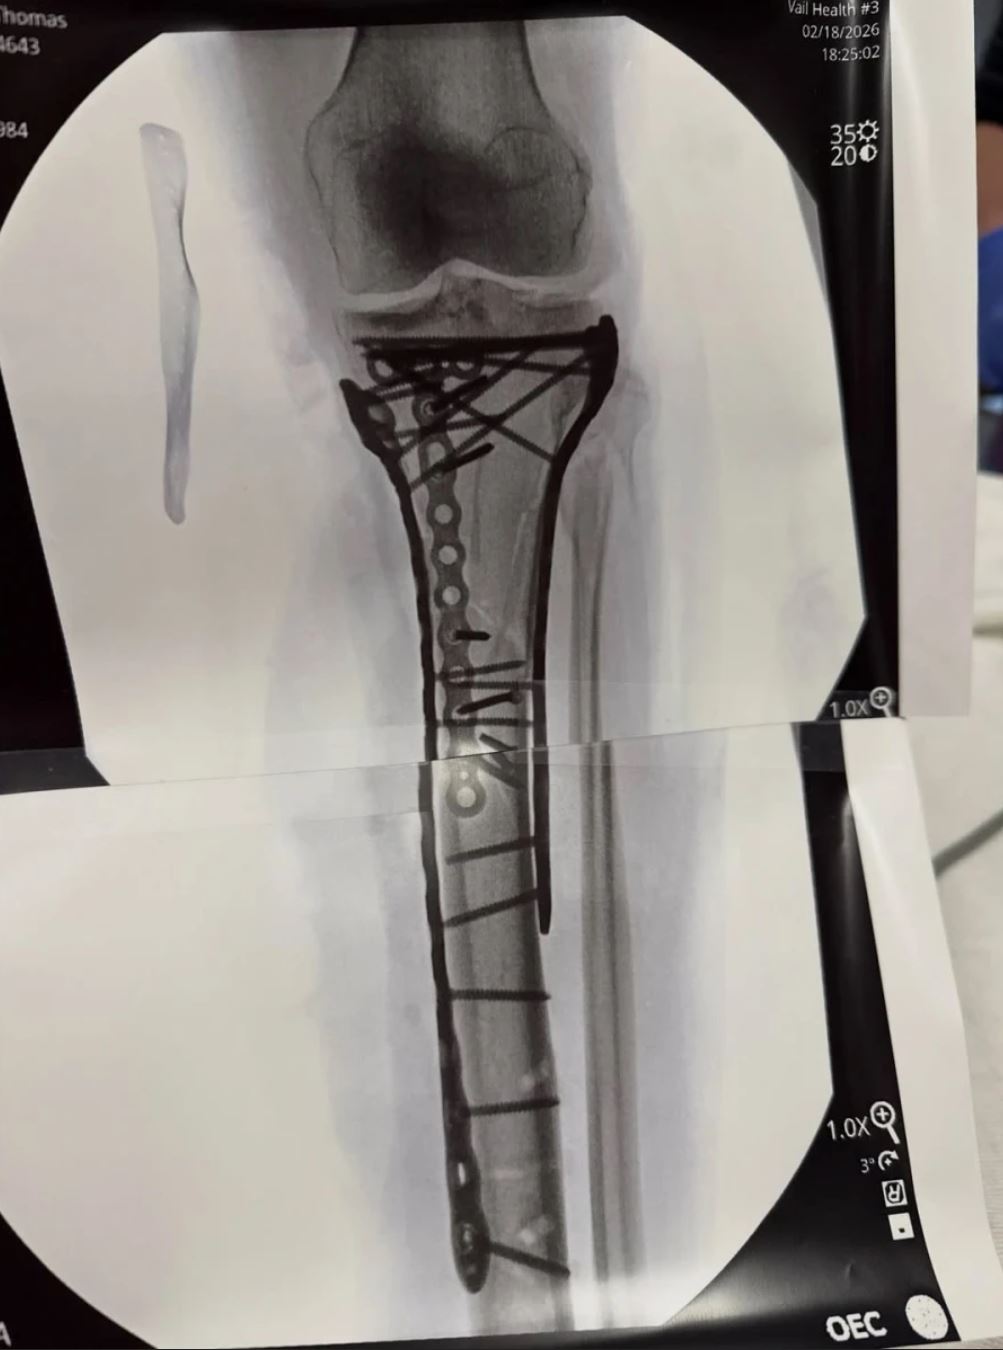

* Η ακτινογραφία από τον τραυματισμό της Βον

Η αποθεραπεία της Λίντσεϊ Βον πρακτικά ακόμη δεν έχει καν ξεκινήσει. Η ίδια αποκάλυψε στο βίντεο ότι θα χρειαστεί περίπου ένας χρόνος για να επουλωθούν τα κατάγματα στα οστά της, όπως άλλωστε φαίνεται και από τις σοκαριστικές ακτινογραφίες της. Ακολούθως, θα κληθεί να αποφασίσει αν θα αφαιρεθούν τα μέταλλα από το πόδι της, κάτι που φυσικά θα απαιτεί νέα επέμβαση. Ακολούθως, όταν όλα αυτά θα έχουν συμβεί, τότε θα πρέπει να αποκατασταθεί και ο τραυματισμός στον πρόσθιο χιαστό.